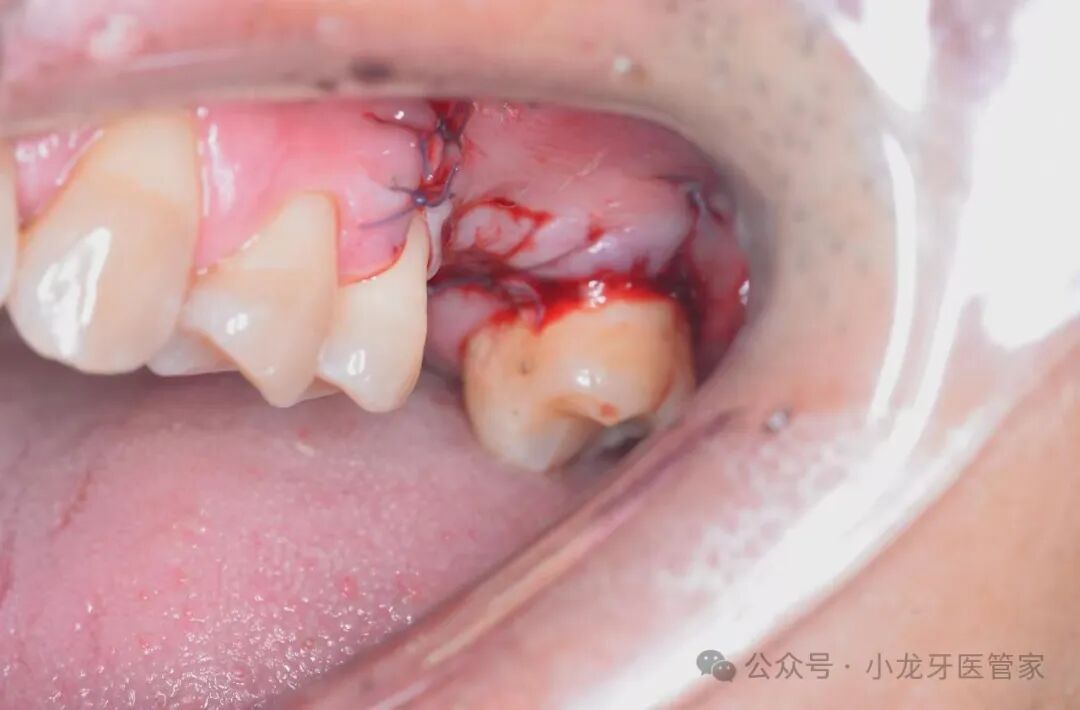

局部聚维酮碘消毒,适量4%阿替卡因局部浸润麻醉。牙槽嵴顶偏颊侧行水平切口,附加垂直松弛切口;全厚瓣翻瓣暴露上颌窦外侧壁;利用登腾DASK上颌窦提升工具行椭圆形骨窗;精细剥离窦底黏膜并完整提升;植入0.75g去蛋白牛骨矿化基质(Bio-Oss);覆盖可吸收胶原膜(Bio-Gide);减张,间断缝合,术区加压包扎。

术中图片